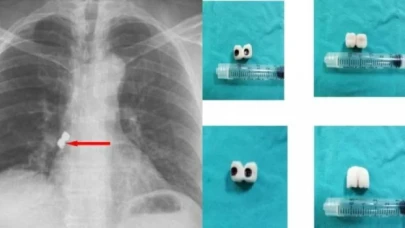

Afyonkarahisar’da, bir şahsın soluk borusuna diş tedavisi sırasında 2 implant kaçtı